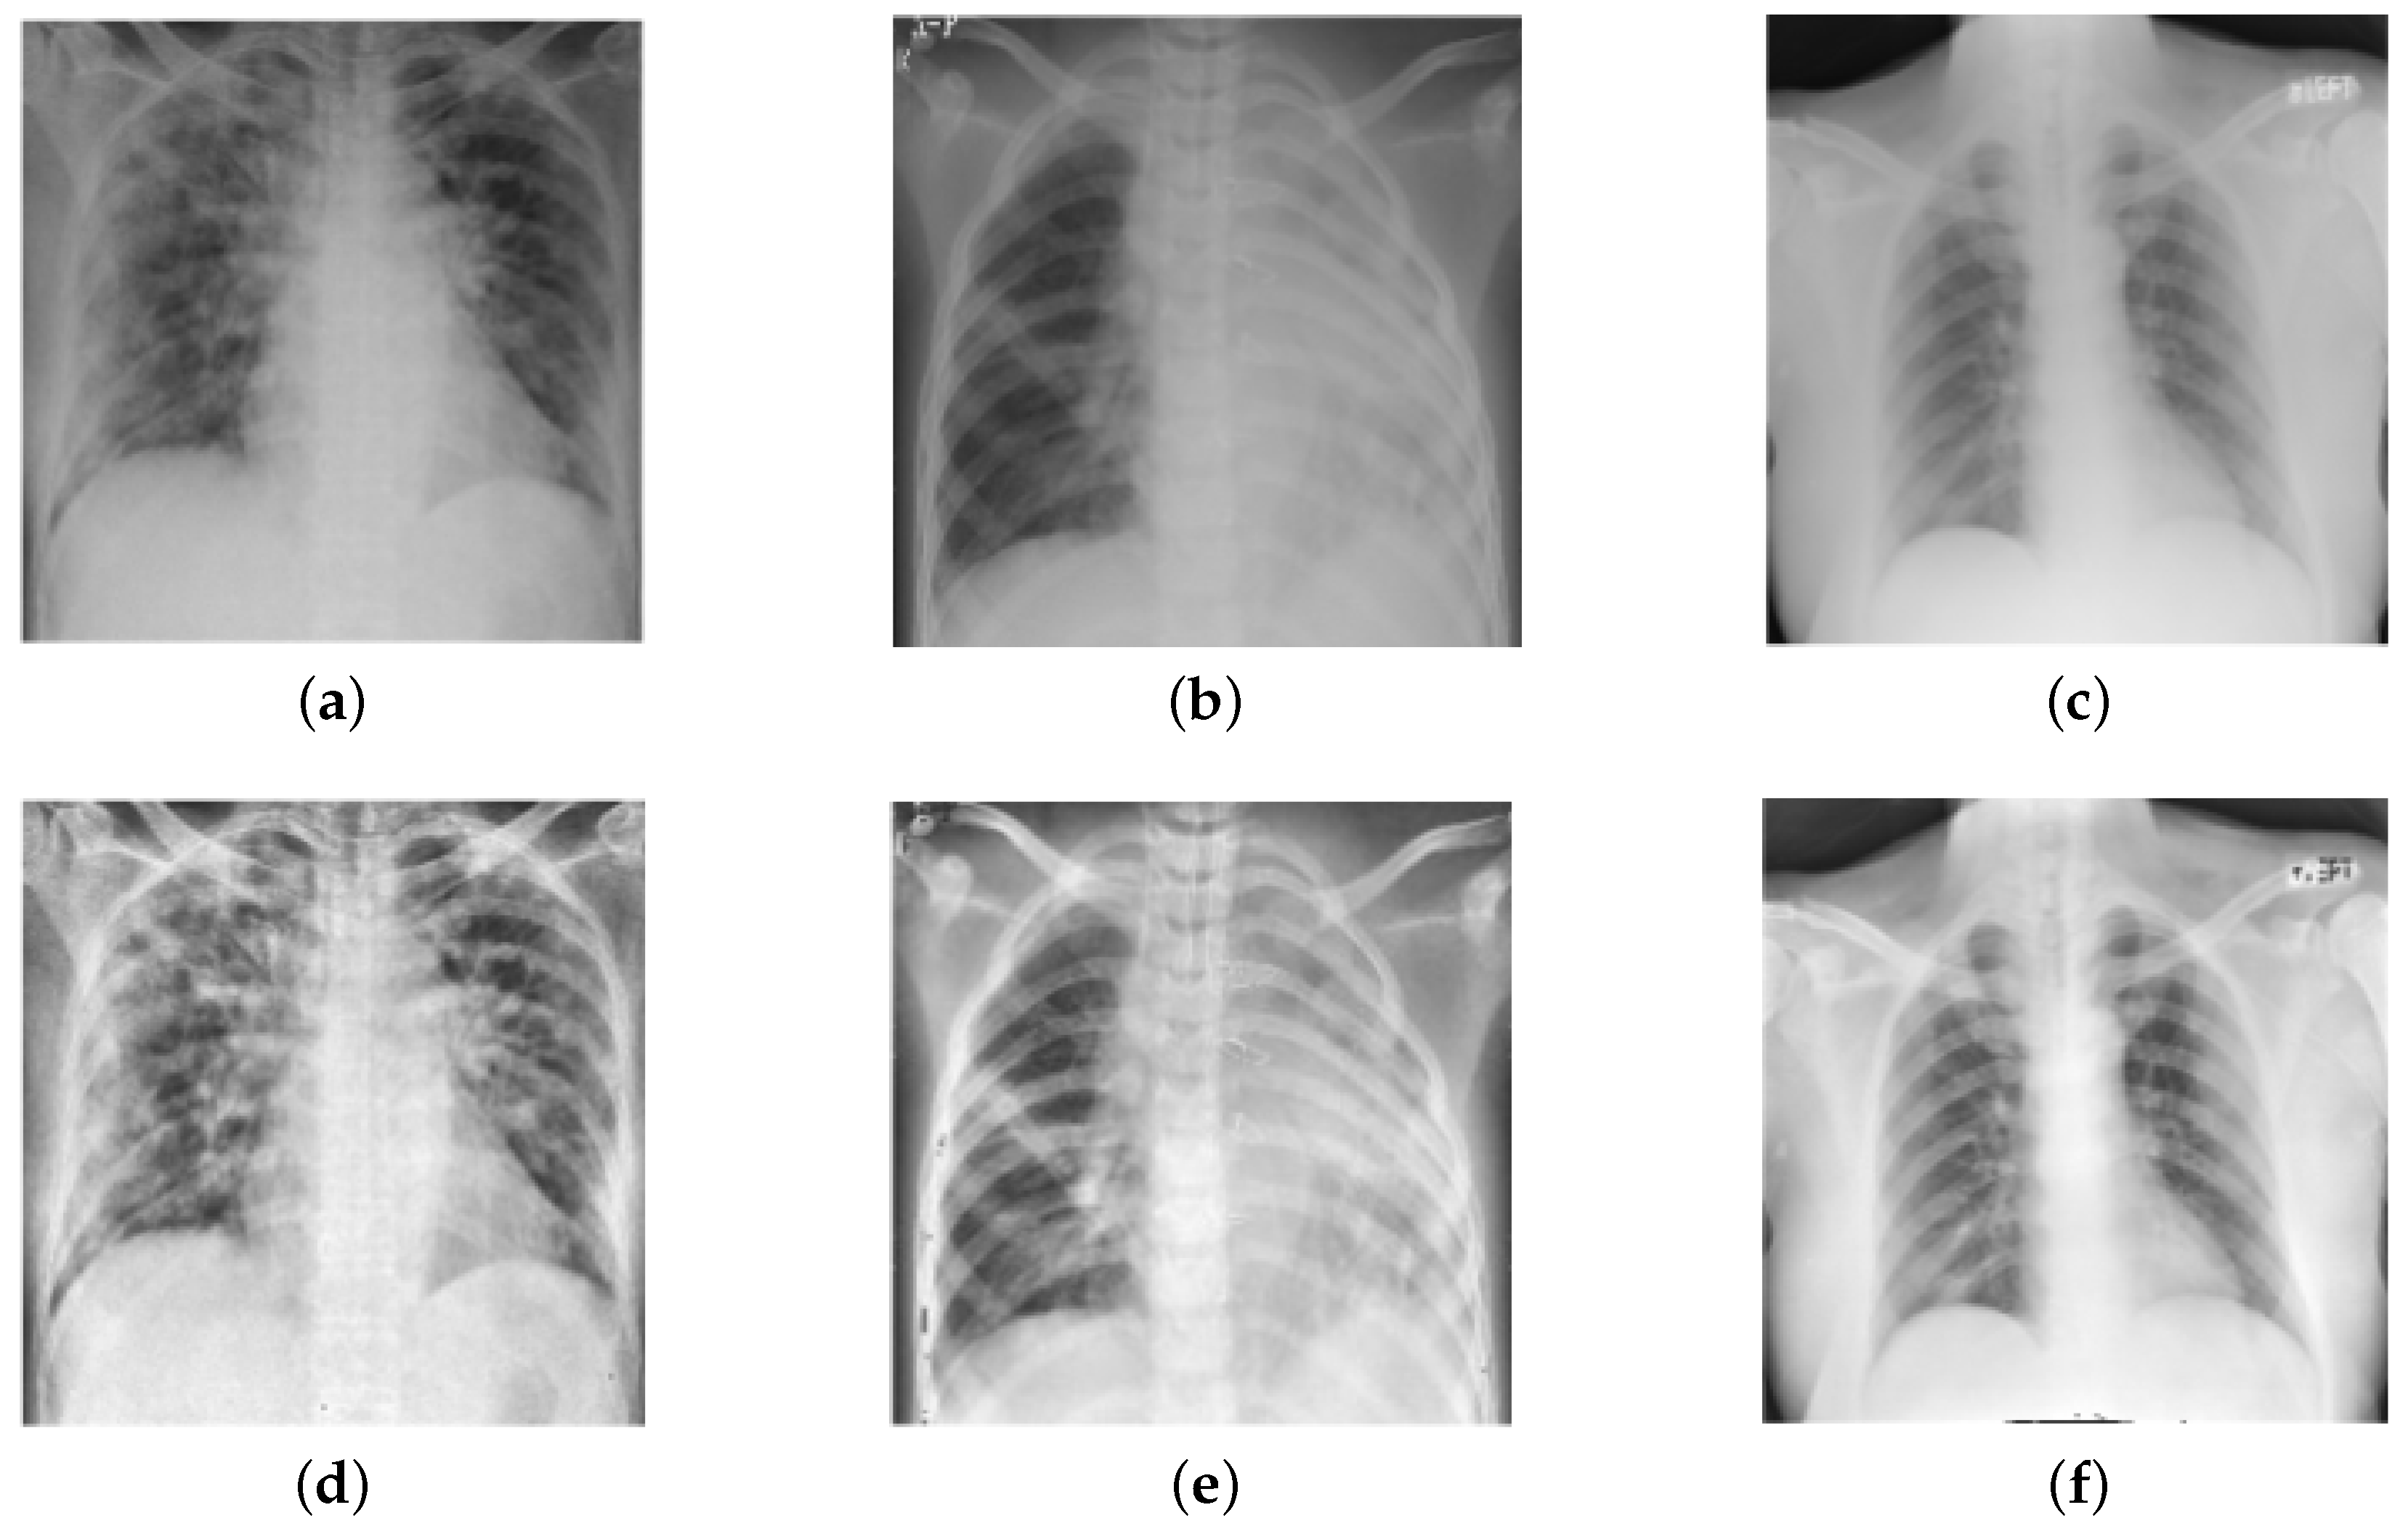

To further verify the efficacy of the proposed model, we considered another dataset COVIDx-V7A (termed as Dataset-2 in this study) which comprises 15,999 CXR images from 15,122 patients across 51 countries and is the largest open-access dataset available to date [22]. These images were collected from five different data repositories and are available at https://github.com/lindawangg/COVID-Net, accessed on 21 November 2022. Table 1 shows the detailed specification of the considered datasets. The samples of a few frontal-view CXR images of different classes from Dataset-1 are presented in Figure 1.

Figure 1.

Frontal-view CXR samples of three categories: (a) Normal, (b) Pneumonia, and (c) COVID-19.